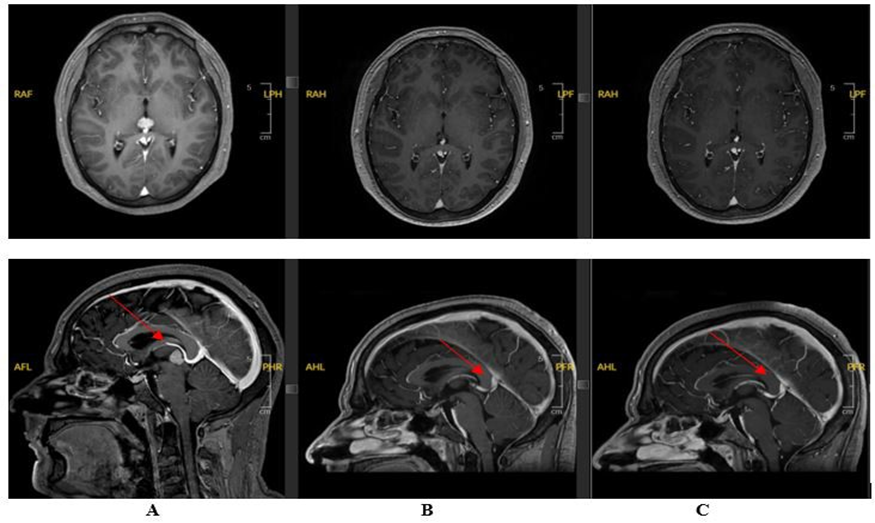

A brain MRI revealed a 15 x 10 x 12 mm mass in the pineal gland, exhibiting isointense signal characteristics on both T1 and T2 sequences, with intense enhancement and subtle heterogeneity following gadolinium injection. Radiological assessment of the spinal cord and conus medullaris was unremarkable, with no abnormal contrast enhancement. Lumbar puncture revealed no malignant cells, and the analysis of tumor markers (both in the serum and cerebrospinal fluid) showed a slight elevation in human chorionic gonadotropin (hCG), with normal alpha-fetoprotein (AFP) levels. Biopsy of the lesion confirmed the diagnosis of a pineal gland germinoma, demonstrating tumor markers consistent with germ cell origin (positive Mast/stem cell growth factor receptor (C-kit or CD117), weakly positive placental alkaline phosphatase (PLAP), partially positive beta human chorionic gonadotropin (β-HCG) and negative AFP).

The patient underwent curative chemotherapy according to the VIP protocol, administered every 3 weeks for 3 cycles. He tolerated the systemic treatment well, and a follow-up MRI of the brain at 1 month after completion of chemotherapy showed a partial response with a small area of residual contrast enhancement. Despite additional imaging sequences (phlebo-MRI and high-resolution 3DT2), this finding was suggestive of either a vascular structure or tumor rest. The patient then received ventricular radiotherapy (proton therapy) with sequential boost to the residual tumor.

Follow-up brain MRI at 3 and 6 months after end of treatment showed stability of a small area of contrast enhancement in the anterior pineal region, with no evidence of germinoma recurrence interpreted as a vascular lesion, and further complete response. Serum tumor markers, including HCG, were normal after chemotherapy as well as alpha-fetoprotein, which remained in normal limits. Following the European Reference Network for rare adult solid cancers (EURACAN) guidelines (2) and after multidisciplinary consultation, radiological surveillance will proceed with quarterly brain MRIs for the first year, followed by semiannual imaging if no recurrence is detected.

Figure 1: Cerebral MRI: A : At the time of diagnosis; B : 1 month after chemotherapy and before proton therapy and C: 3 months after proton therapy.